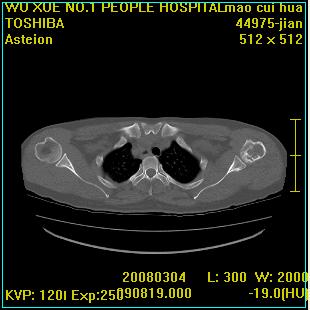

标题: CT12025:男,50岁,左肩活动受限半年。 [打印本页]

标题: CT12025:男,50岁,左肩活动受限半年。

能有x线平片就好了。肱骨头骨结构有破坏。

肩关节骨质破坏呈小囊状,其周软组织轻度肿胀,余未见异常。

考虑:肩袖损伤。建议mri。

左侧肱骨头密度不均匀,高低混杂,周围软组织略肿胀,考虑结核性病变。

考虑左侧肱骨慢性骨髓炎。

左侧肱骨头密度不均匀,高低混杂,髓腔密度稍高,周围软组织略肿胀,肌间隙模糊,考虑慢性骨髓炎可能。密切结合临床!